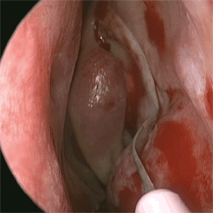

Figure 25-1. Endoscopic view of the injection of the insertion of the middle turbinate. (MT : Middle Turbinate. White arrow points to injection at insertion of middle turbinate. White asterisk show sites of injection along the frontal process of the maxilla). Using a nasal speculum and a headlight, the lateral wall of the nose is infiltrated in the area of the uncinate process and along the frontal process of the maxilla. The insertion and the turbinate itself are also infiltrated, and the area above can also be injected. The nose is packed gently with neurosurgical cottonoids soaked in lidocaine 4% with phenylephrine 0.25%. When surgery is performed under local anesthesia, the packing should include the opening of the nostril to ensure proper anesthesia of the tip of the nose. If this is still sensitive at the time of surgery, a small infiltration of the mucosa of the septum in this area can be done. When surgery is performed under local anesthesia, an infiltration of anesthetic is delivered to the medial canthal area, lacrimal sac area, and the anterior ethmoidal nerve from the orbital side. This step is not necessary under general anesthesia.